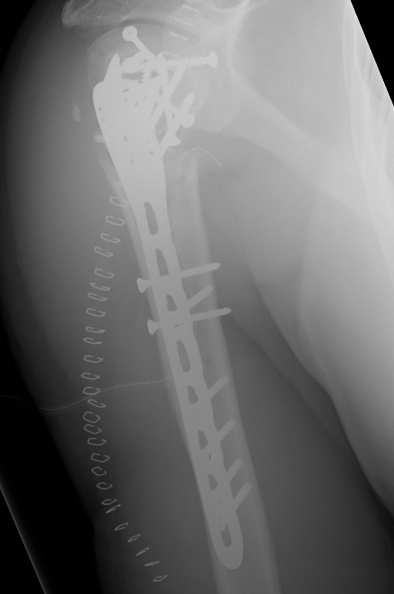

proximal humerus fracture Background ORIF with locking plate Arthroplasty Greater tuberosity fractures Lesser tuberosity fractures / avulsions Book traversal links for Proximal humerus fractures ‹ Pectoralis Major Tears Up Background ›